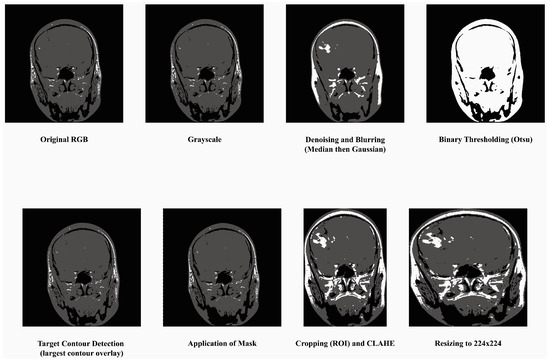

- Convert to Grayscale: Most MRI datasets are in grayscale or captured using only intensity-based information, while some datasets may also include unnecessary color channels (from RGB formats). Converting them to grayscale ensures uniformity in data representation and reduces computation by eliminating redundant information. The process has been done by grayscale using OpenCV’s cv2.cvtColor function. This step also helps focus the model on texture and contrast, which are critical for identifying tumor regions in medical imaging.

- Denoising and Blurring: MRI images often contain artifacts or noise due to acquisition methods, which can obscure key tumor features. Median filtering reduces random noise, preserving the edges and fine details critical for classification without distorting important structures like tumor contours. Blurring is applied to smooth the image and reduce high-frequency variations unrelated to tumors. It helps in suppressing minor unrelated details (e.g., scanner irregularities) and enhances the model’s ability to focus on regional features of tumors rather than noise.

- Binary Thresholding: Binary thresholding creates a clear separation of foreground (possible tumor areas) and background, which aids in isolating the tumor region. By emphasizing areas of interest based on intensity standards, this step generates a mask for tumors, facilitating structured feature extraction and segmentation. The method was applied using a fixed threshold value of 127. This process created a binary mask for tumor region selection. For normalization, pixel intensity ranges were scaled between 0 and 1 prior to thresholding.

- Target Contour Detection: After applying the binary mask, it is essential to extract the tumor region accurately. The contour detection algorithm identifies and segments the largest connected region (potential tumor) and removes non-relevant regions such as background noise or anatomical elements outside the tumor that has been done using findContours function in Python’s OpenCV library. That finds the largest contour by area greater than 500 pixels was selected as the tumor region. This ensures the model focuses on the most relevant part of the image.

- Application of Mask: The binary mask is directly applied to filter out regions irrelevant to the tumor. It allows the model to operate only on imaged regions that likely hold tumor information, improving classification accuracy and computational efficiency.

- Cropping, CLAHE: After isolating the tumor, extracting the region of interest (ROI) eliminates unnecessary background, allowing the model to focus entirely on meaningful features while standardizing input dimensions. This technique enhances the contrast of the tumor region by redistributing brightness in the image, helping highlight subtle details. CLAHE with clip limit = 2.0, grid size = (8 × 8), that reduces the inter-image variability caused by differences in MRI scanner settings, patient anatomy, or lighting conditions, which are particularly important for tumor region detection [48].

- Resizing: To ensure compatibility with the MobileNetV2 architecture, all images are resized to a fixed dimension of 224 × 224 pixels. This step provides uniformity in input size, reduces computational demands, and ensures that the model processes images efficiently without distortion.